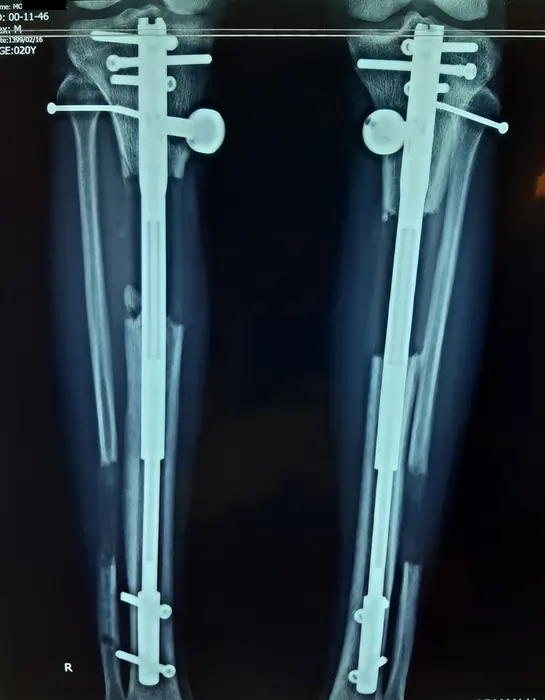

نمونه رادیولوژی افزایش قد ساق با روش MTN (بیمار ۲۰ ساله آقا)

در این تصاویر روند افزایش قد ساق با میله تلسکوپی MTN در یک بیمار ۲۰ ساله را میبینید. در رادیوگرافی قبل از عمل، طول هر دو تیبیا در محدوده ۳۴۳ میلیمتر اندازهگیری شده است. پس از جراحی، میله تلسکوپی MTN داخل هر دو ساق قرار گرفته و استخوان در ناحیه میانی برش داده شده است.

در هفتههای بعد، بیمار روزانه با استفاده از پیچ MTN حدود یک میلیمتر به طول استخوان اضافه کرده است. در رادیوگرافی میانی، فاصله ایجاد شده در محل استئوتومی حدود ۲۰ میلیمتر است و کالوس اولیه در اطراف شکاف دیده میشود. در تصویر بعدی، افزایش طول به حدود ۶٫۸ سانتیمتر رسیده و استخوان جدید تقریباً تمام شکاف را پر کرده است.

در رادیوگرافی نهایی، هر دو ساق هممحور هستند، فضای استئوتومی با استخوان جدید پر شده و طول نهایی ساقها نسبت به قبل از عمل حدود ۶–۷ سانتیمتر بیشتر است. این کیس نشان میدهد که با رعایت برنامه کشش، فیزیوتراپی و کنترل رادیولوژیک منظم، میتوان افزایش قد قابلتوجهی را با حفظ هممحوری اندام و پایداری ایمپلنت بهدست آورد.

(نتایج هر بیمار منحصر بهفرد است و میزان افزایش قد و سرعت جوش خوردن استخوان میتواند متفاوت باشد.)

در این بیمار، هممحوری مکانیکی ساقها حفظ شده و کالوس متراکم در ناحیه استئوتومی دیده میشود.

نتایج در افراد مختلف متفاوت است.